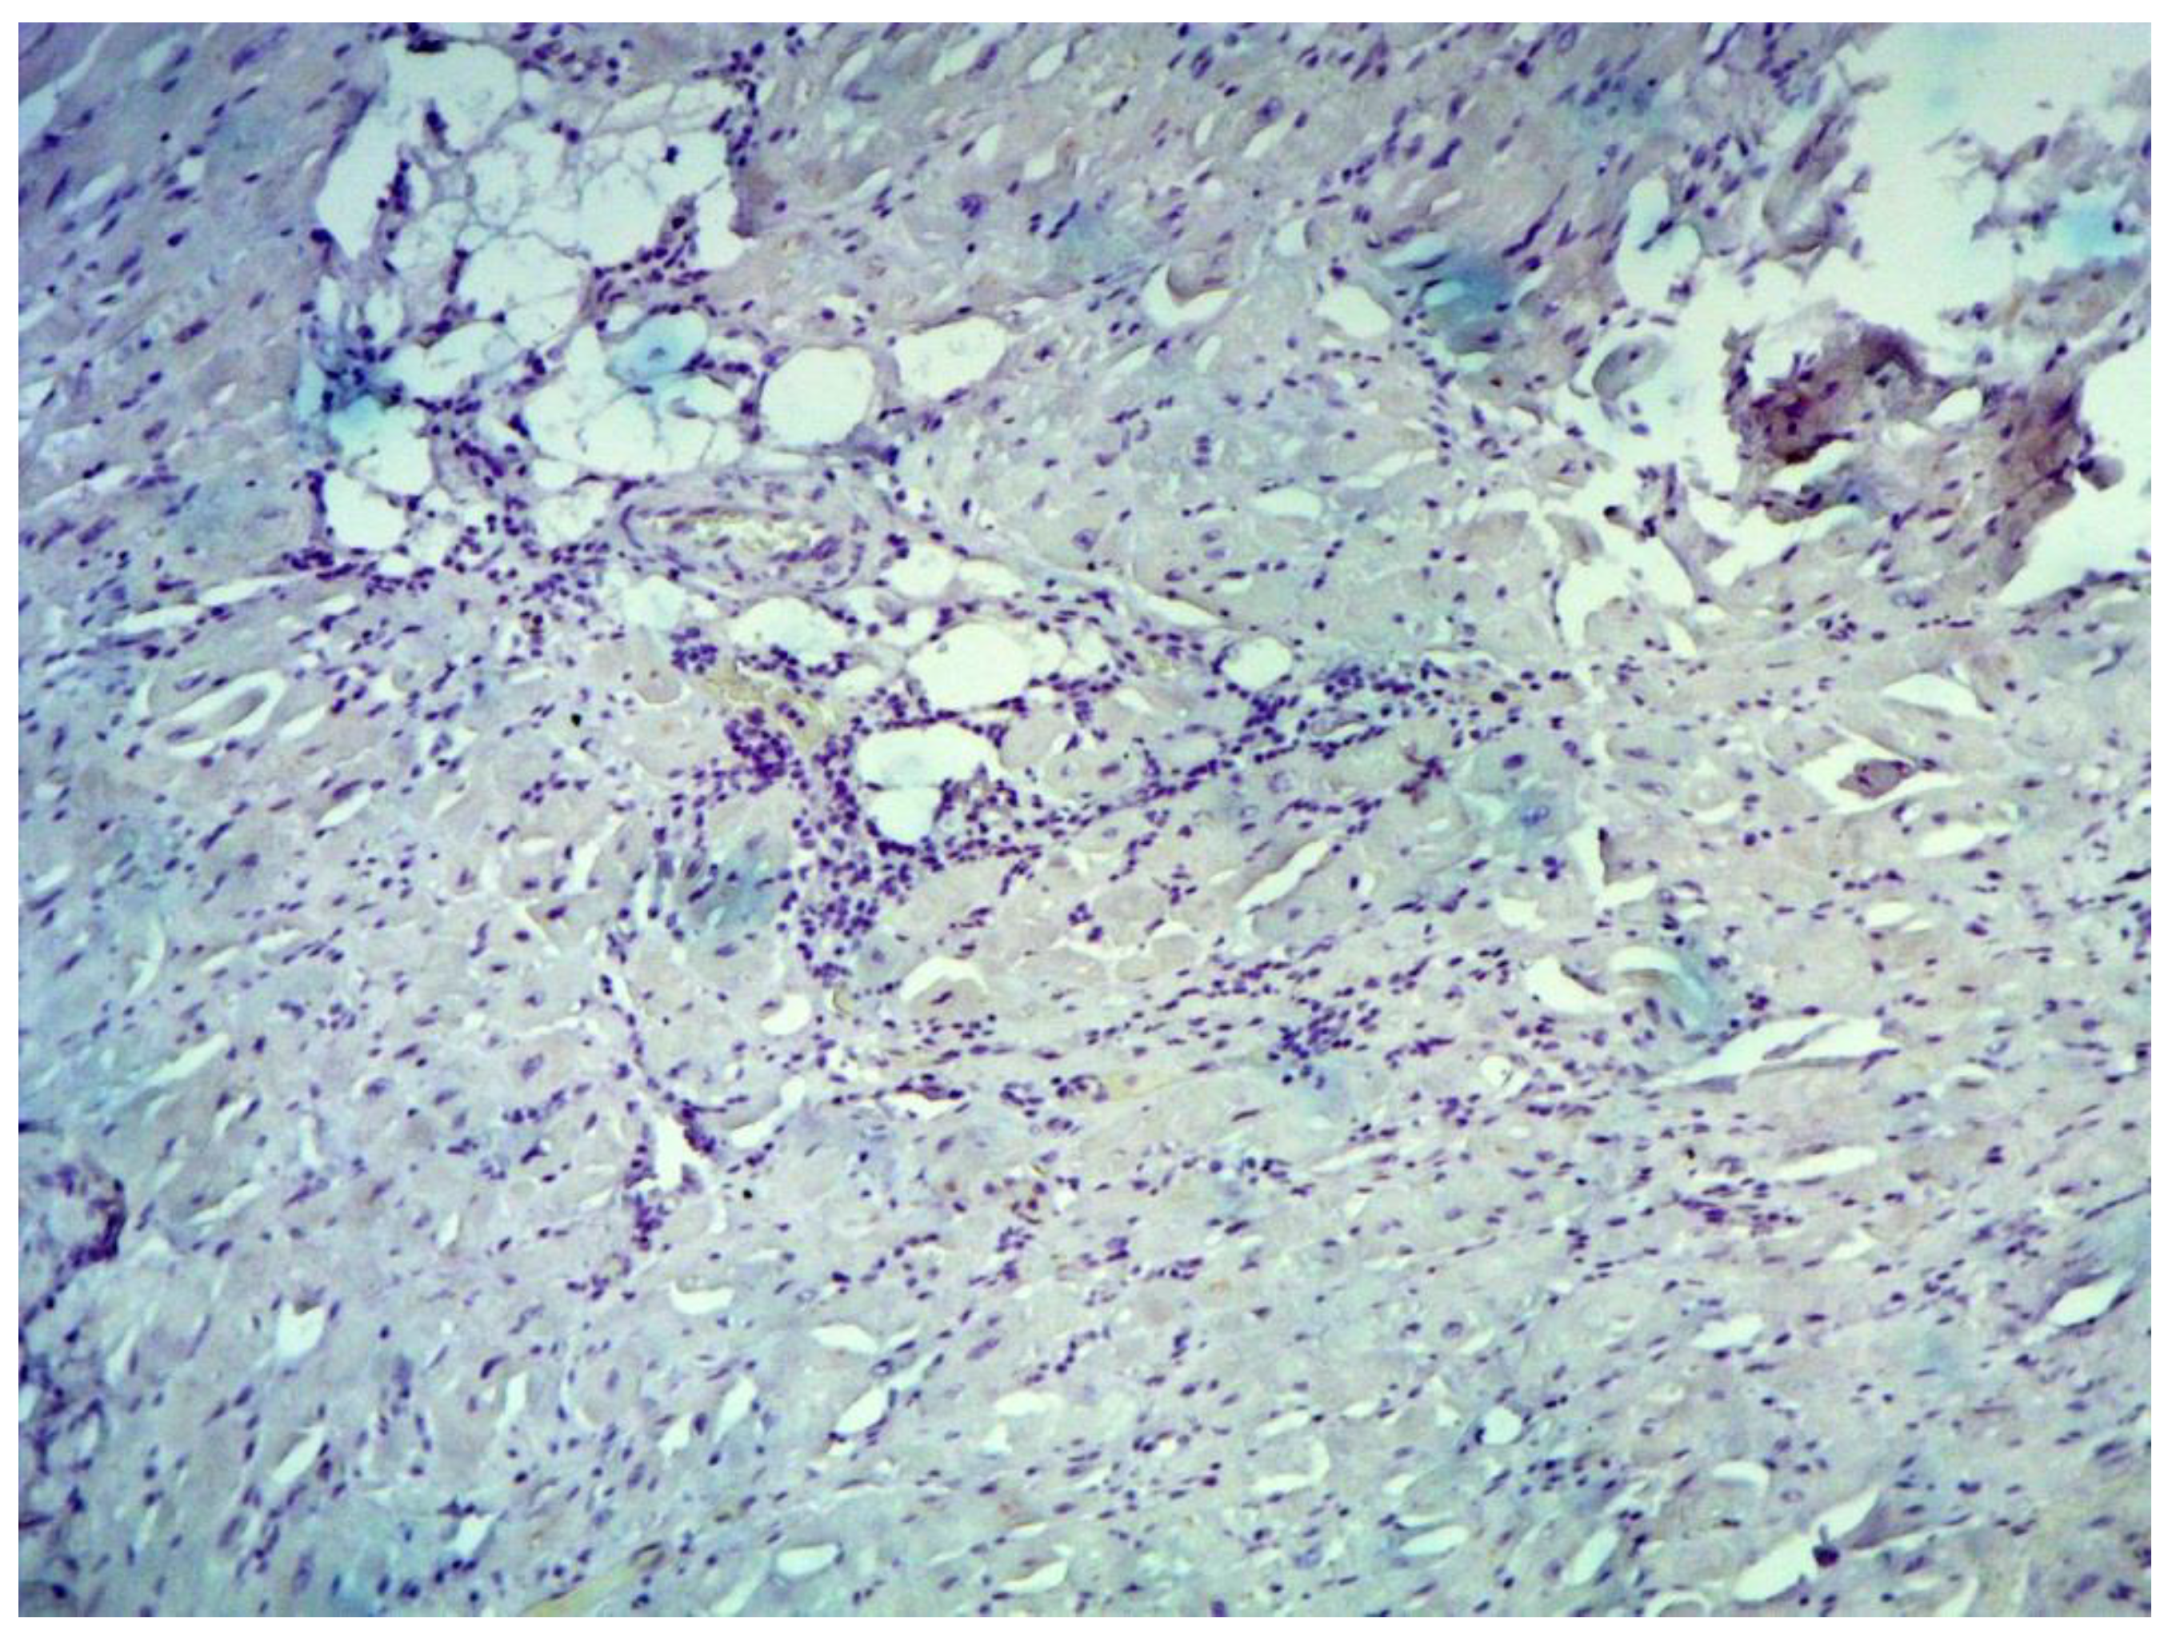

Inflammatory changes in the myocardium were detected in 32 patients (47.8%), including nine patients (28.1%) with lymphocytic infiltration of less than 14 lymphocytes per mm2 (Figure 4 and Figure 5). The data obtained with EMB from RV and IAS were comparable. Inflammatory changes in RV correspond to a similar finding in IAS, while fibrotic changes in RV correspond to the same evidence in IAS. According to the results of immunohistochemical analysis, the virus expression was detected in one of these patients (3.1%). A combination of human herpes simplex virus type 2 and Epstein-Barr was found. No virus expression was detected in the remaining patients.

Figure 4. Endomyocardial infiltration with CD3+ lymphocytes. Immunohistochemical study, antibodies to the Epstein-Barr virus, ×200.